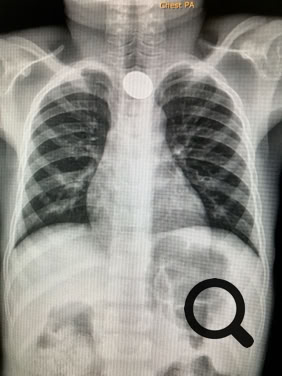

In the print version of the book there are many black and white images. The full colour versions are found in the gallery below. Depending on your connection performance the enlarged images may take a little time to load.